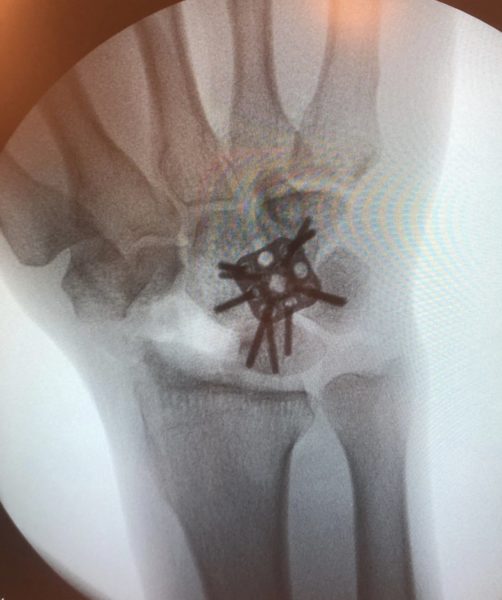

A artrodese dos quatro cantos é indicada nas artroses mediocárpicas geradas por:

APseudoartrose de escafoide

CDoença de Kienbock